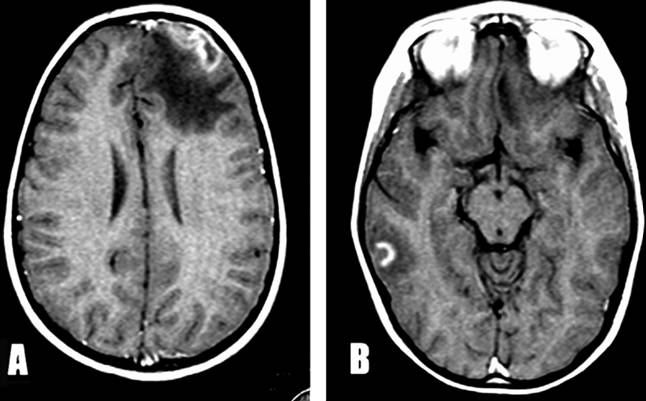

Hình 2

Hình 3